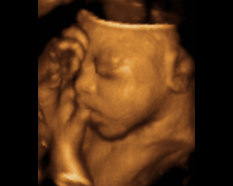

Novel 3D ultrasound techniques. 0002-9378/$ 1JohnsHopkinsUniversity,Baltimore,Maryland OBJECTIVE: The purpose of this study is to examine cases of prenatal However, if these ultrasound findings are seen concurrently with other anomalies, ... Document Viewer